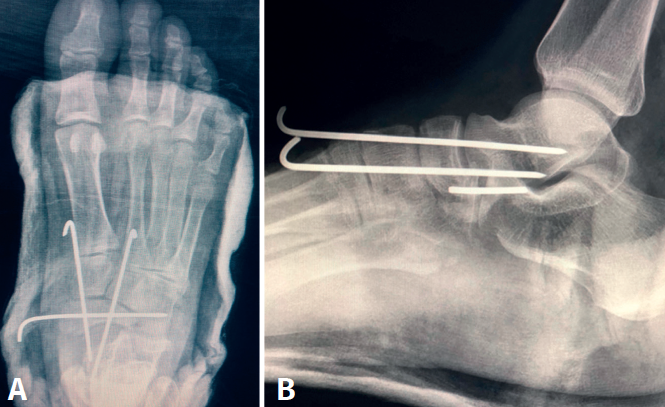

rpt.3601.fs2110026-figura3.png

Figura 3. A: disposición de las agujas de Kirschner posquirúrgica, visión dorsal; B: disposición de las agujas de Kirschner posquirúrgica, visión lateral.

Tras el estudio preoperatorio y la valoración anestésica del paciente, se realizó cirugía a los 4 días del accidente, después de mejorar la inflamación y el edema del pie. Se iniciaron maniobras de reducción cerrada, que lograban la reducción, mediante una maniobra de flexión de la rodilla, posición del pie en ligera flexión dorsal con tracción longitudinal de los metatarsianos y opresión intensa dorsal sobre el escafoides. Manteniendo dicha posición, se realizó estabilización con 3 agujas de Kirschner: la primera de dorsal a plantar a través de la primera cuña, pasando por el escafoides y la cabeza del astrágalo; la segunda ligeramente medial a través de la primera cuña, atravesando el escafoides y la cabeza del astrágalo; por último, la tercera aguja de Kirschner insertada medialmente de escafoides a cuboides (Figura 3)